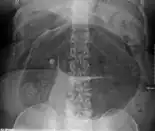

Plain X ray of a cecal volvulus

- Abdominal x-ray – tire-like shadow arising from right iliac fossa and passing to left

After taking a thorough history, the diagnosis of colonic volvulus is usually easily included in the differential diagnosis. Abdominal plain x-rays are commonly confirmatory for a volvulus, especially if a coffee bean sign is seen. These refer to the shape of the air-filled closed loop of colon which forms the volvulus. Should the diagnosis be in doubt, a barium enema may be used to demonstrate a "bird's beak" at the point where the segment of proximal bowel and distal bowel rotate to form the volvulus.